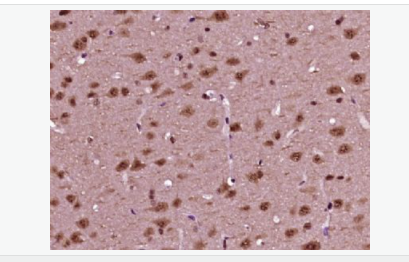

交叉反應(yīng):Human,Mouse,Rat(predicted:Pig,Cow,Sheep) 推薦應(yīng)用:WB,IHC-P,IHC-F,ICC,IF,ELISA

| 產(chǎn)品應(yīng)用 | WB=1:500-2000 ELISA=1:5000-10000 IHC-P=1:100-500 IHC-F=1:100-500 ICC=1:100-500 IF=1:100-500 (石蠟切片需做抗原修復(fù)) not yet tested in other applications. optimal dilutions/concentrations should be determined by the end user. |